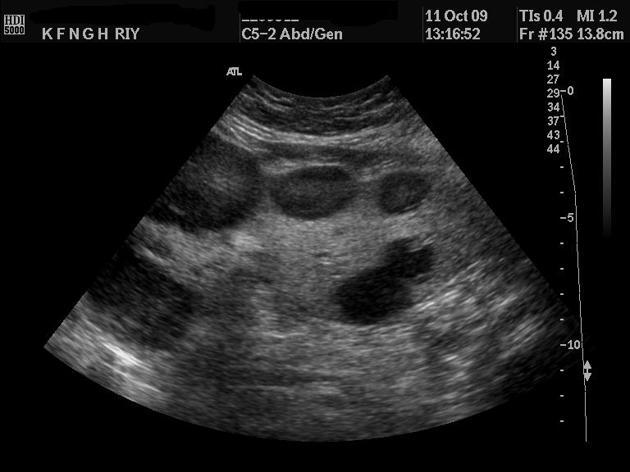

What is Polycystic liver disease?

This is an autosomal dominant genetic disease in which multiple small cysts cover the liver. 60% of patients with polycystic liver disease will have polycystic kidney disease.

What is the sonographic appearance of Polycystic liver disease?

Anechoic

Thin well-defined walls

Posterior

enhancement

Multiple

Varying in small size